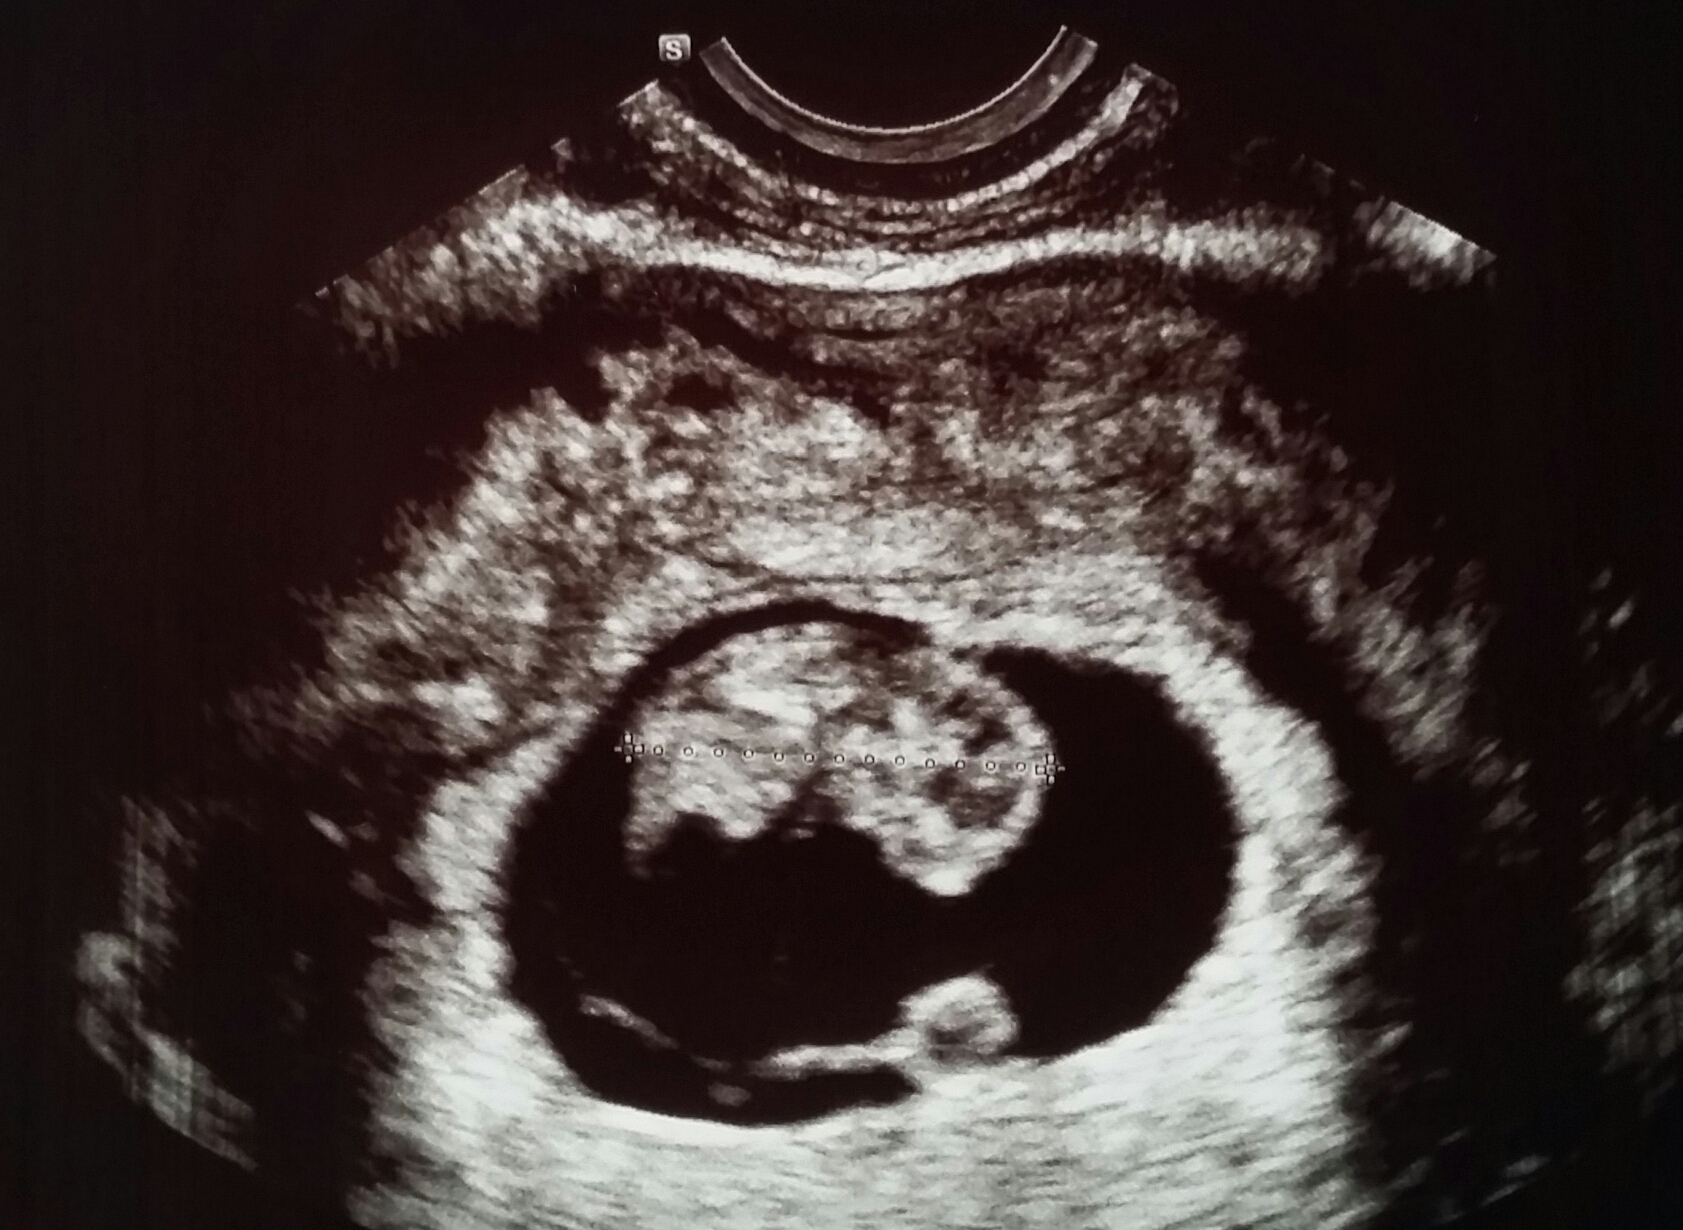

My little bean. According to LMP I was 6wks+5d but baby is measuring 6wks+3. They aren't changing my date yet because the baby is so small the tech said she wasn't sure she was even measuring the whole baby. Hb was 118. I had a 2nd trimester MC in May so I'm going to get to see this bean a lot! ☺️